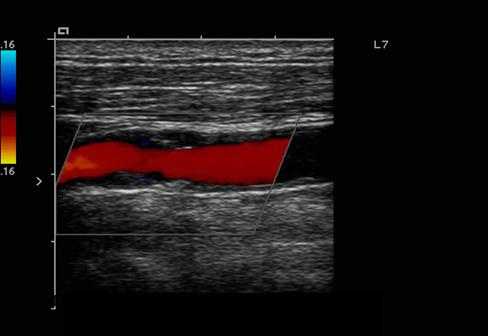

Explain the waveform of the CCA

Mimics both ICA and ECA waveforms

Explain the waveform of the ICA

low resistant - constant forward flow

Forward flow throughout the cardiac cycle

Explain the waveform of the ECA

high resistant

steep forward stroke

Forward flow during systole, low or reverse diastolic component